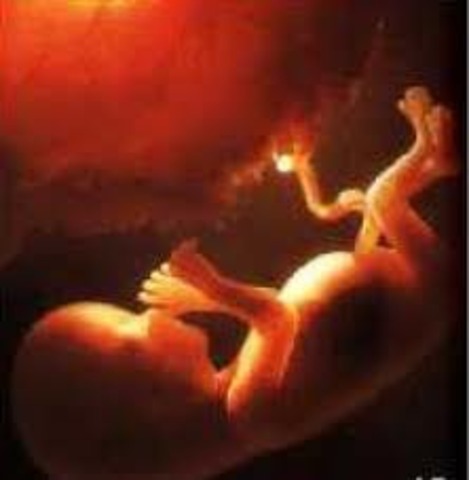

• Week 28

Week 28

Your little work in progress is now about 2.5 pounds and almost 16 inches long. He's busy adding new skills such as blinking to an already impressive repertoire of tricks like coughing, sucking, hiccuping, and taking practice breaths. Your baby's sleep now includes the REM phase — and that means he could be dreaming already.